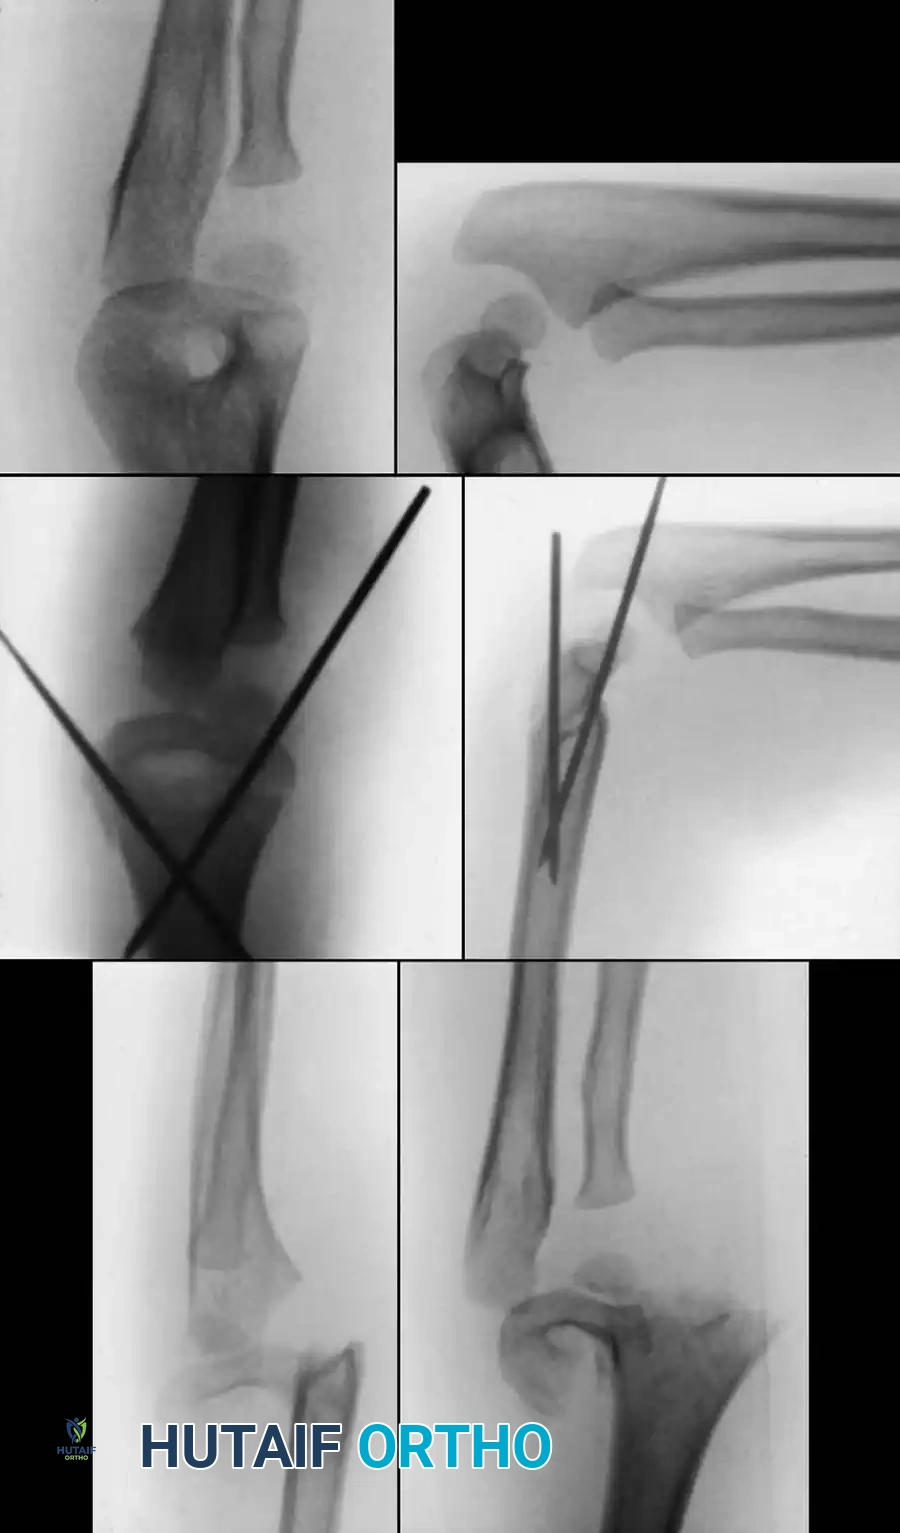

COMPREHENSIVE SURGICAL AND RADIOGRAPHIC ATLAS

The following gallery provides an exhaustive visual reference for the varied presentations, fluoroscopic interventions, and advanced reconstructive techniques associated with pediatric elbow trauma and radial neck fractures.

Preoperative Radiographic Evaluation

Intraoperative Fluoroscopy and Pin Placement

Fig. 33-44 A-D, Reduction of radial head by leverage method and retrograde intramedullary pinning with Kirschner wire.

Gonzalez-Herranz et al. and Metaizeau revolutionized the treatment of displaced radial neck fractures (O’Brien types II and III) using retrograde intramedullary pinning. This technique boasts excellent results in over 94% of cases.